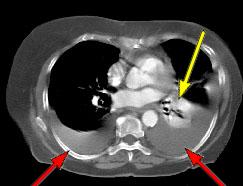

HELICAL CT FINDINGS: The CT was performed on AIC’s multi-slice helical CT (MSCT) scanner. Images with 5 mm collimation were obtained before, immediately following and 5-10 minutes after power injection of IV contrast. Fig. 1 demonstrates large bilateral pleural effusions (red arrows) with secondary compressive atelectasis of the lower lobes (yellow arrow). Fig. 2 shows large amount of ascites (arrows). Fig. 3 shows a large heterogeneous complex pelvic mass (blue arrow) and a large amount of peritoneal masses consistent with omental metastasis known as “omental caking” (green arrows).